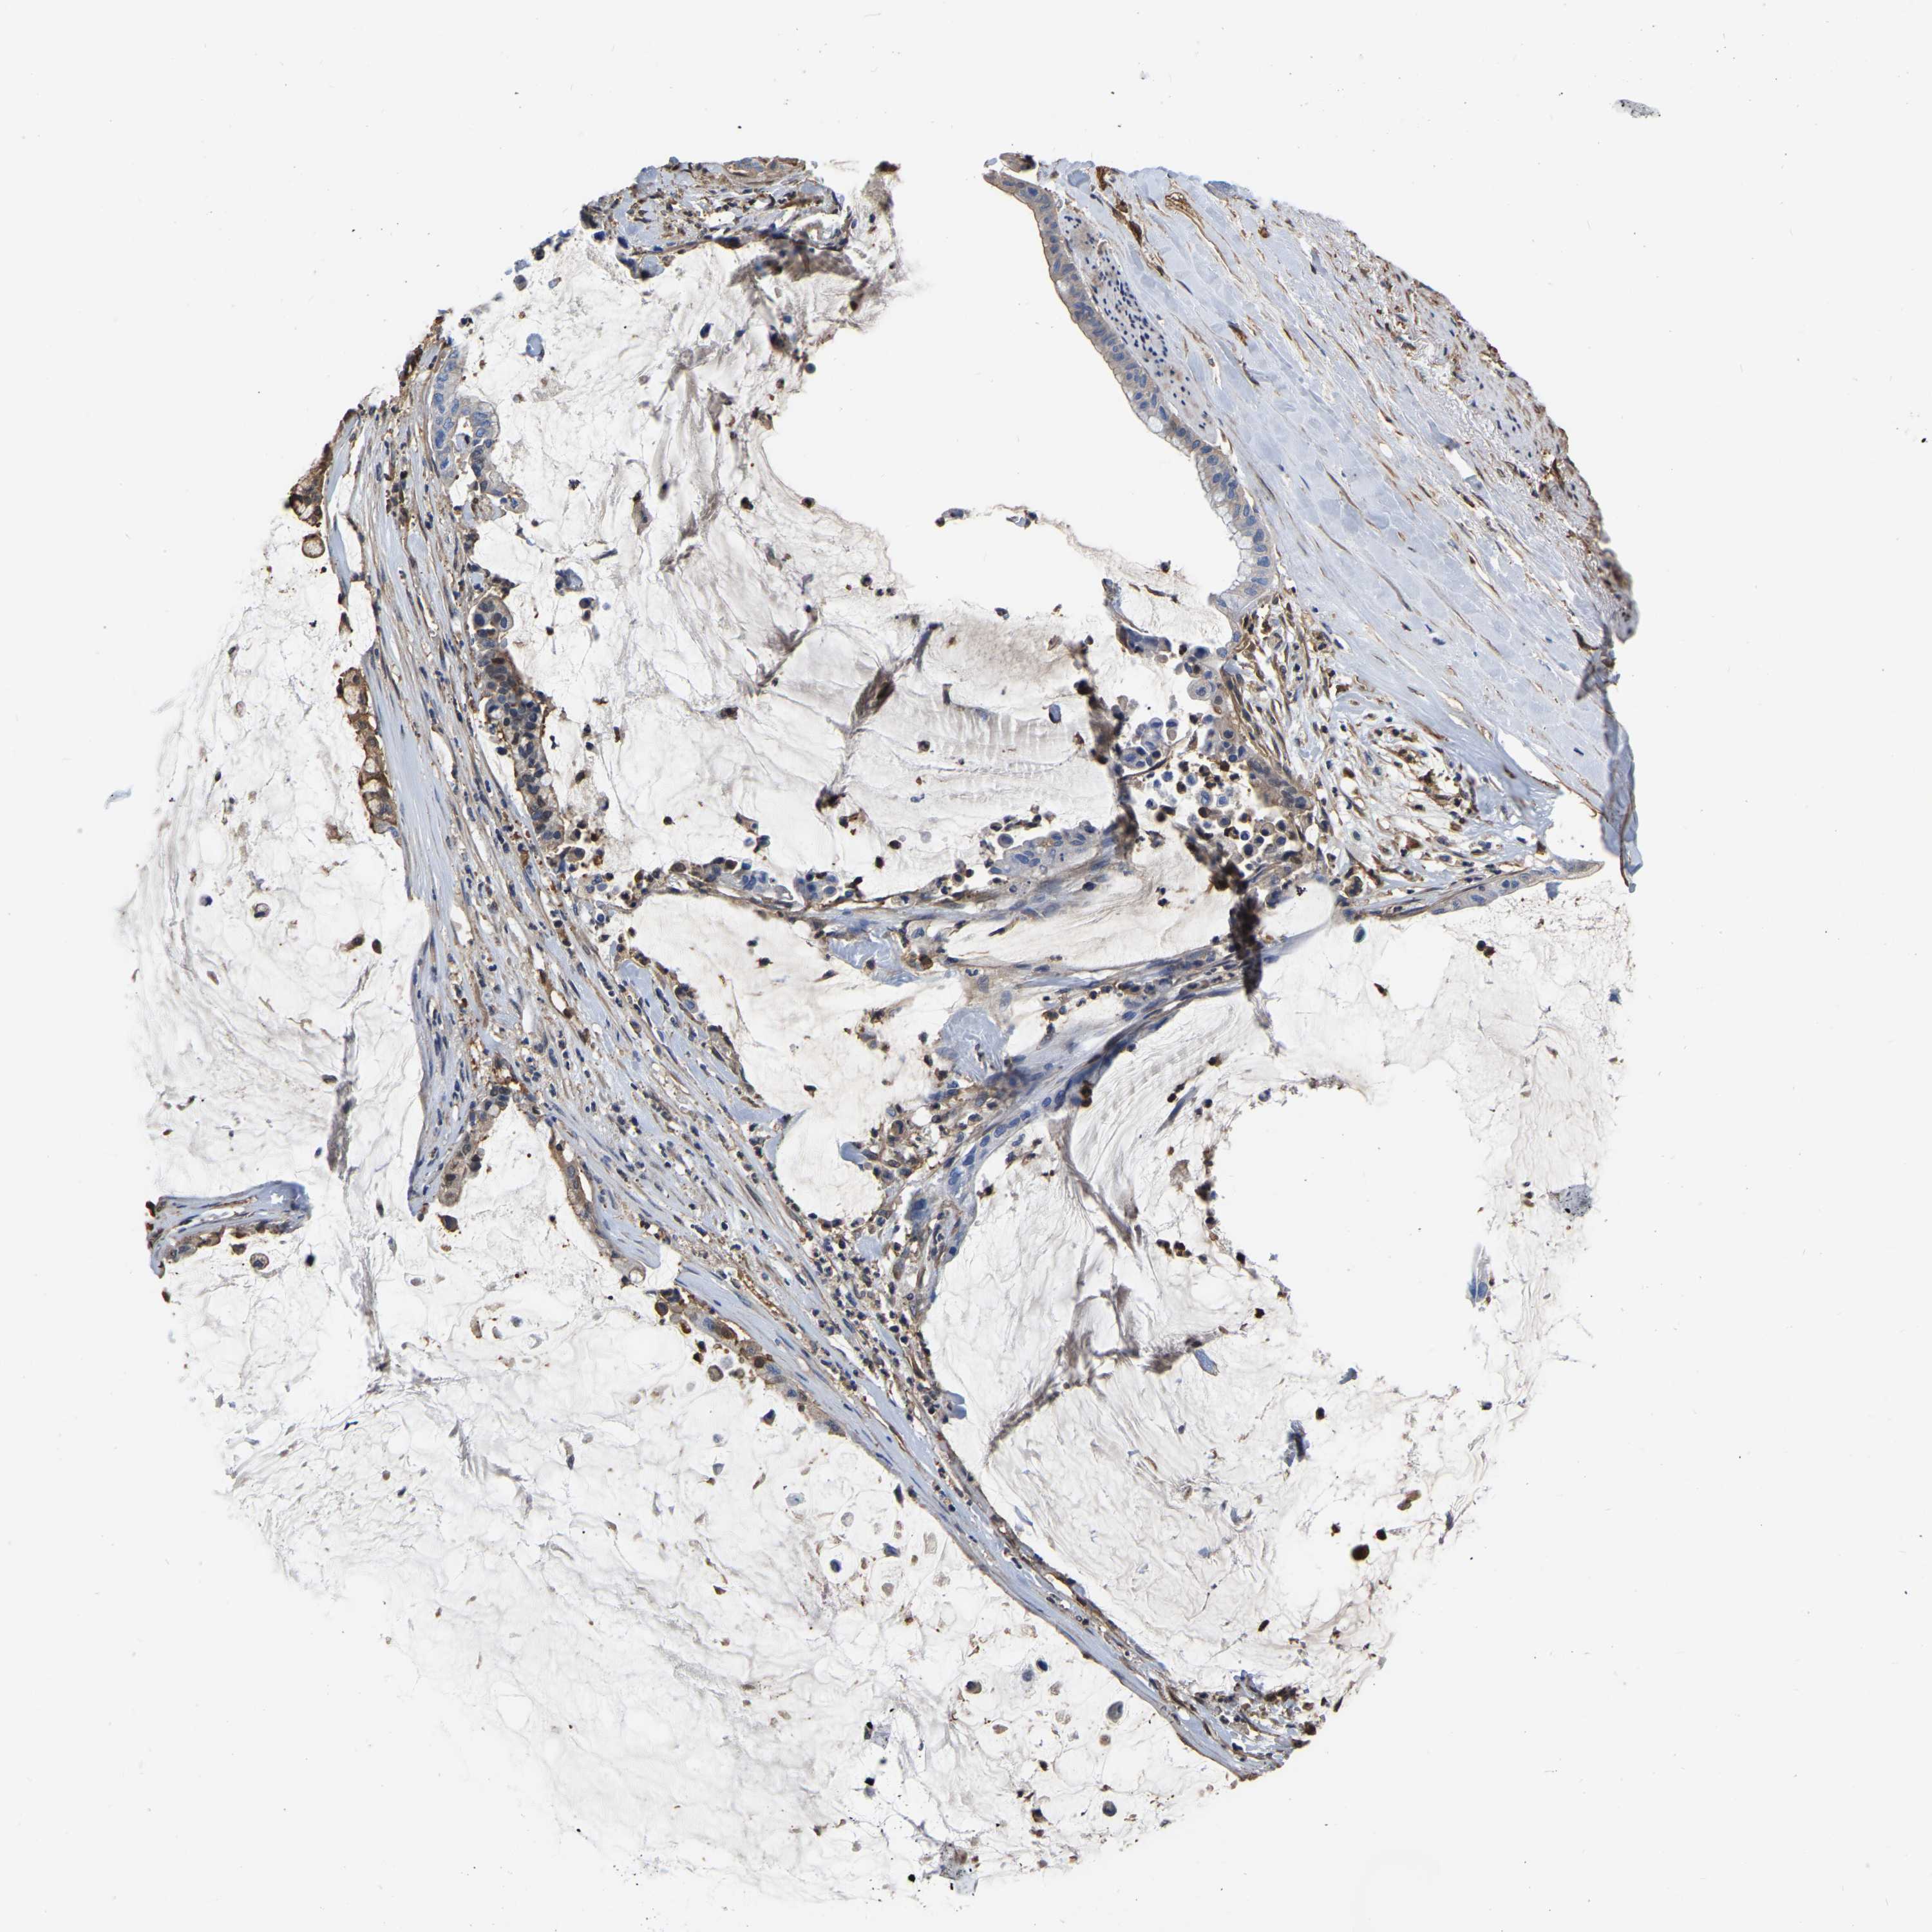

PANCREATIC CANCER - Protein expressioni

A mouse-over function shows sample information and annotation data. Click on an image to view it in a full screen mode. Samples can be filtered based on level of antibody staining by selecting one or several of the following categories: high, medium, low and not detected. The assay and annotation is described here.

Note that samples used for immunohistochemistry by the Human Protein Atlas do not correspond to samples in the TCGA dataset.

Antibody stainingi

Antibody staining in the annotated cell types in the current human tissue is reported as not detected, low, medium, or high, based on conventional immunohistochemistry profiling in selected tissues. This score is based on the combination of the staining intensity and fraction of stained cells.

Each image is clickable and will lead to virtual microscopy that enables deeper exploration of all samples and also displays staining intensity scores, fraction scores and subcellular localization as well as patient and tissue information for each sample.

Antibody HPA019007

Antibody CAB004641

Staining

High

Medium

Low

Not detected

Intensity

Strong

Moderate

Weak

Negative

Quantity

>75%

75%-25%

<25%

None

Location

Nuclear

Cytoplasmic/membranous

Cytoplasmic/membranous,nuclear

Adenocarcinoma, NOS

Adenocarcinoma, metastatic, NOS